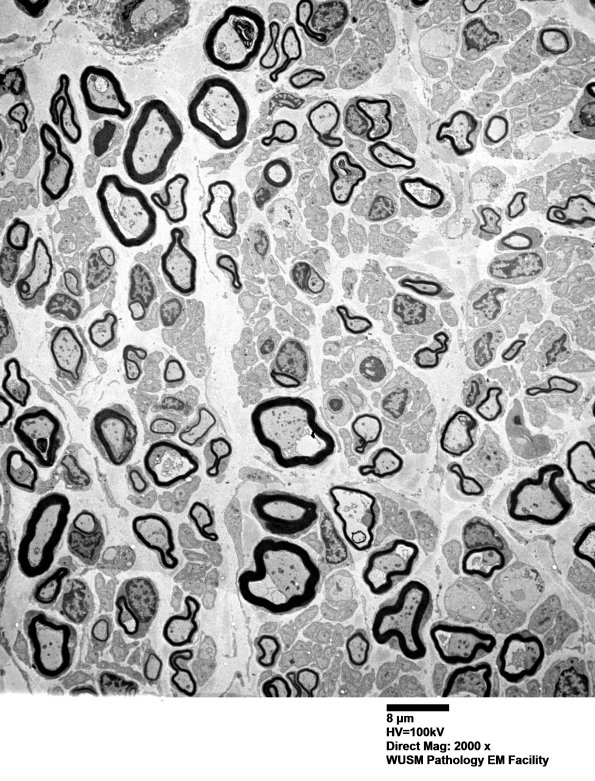

6B1,2 These low magnification images show developing bimodal populations of large and small myelinated axons which look discrete; however, there are numerous developing axons with myelination still ongoing. (electron micrographs)